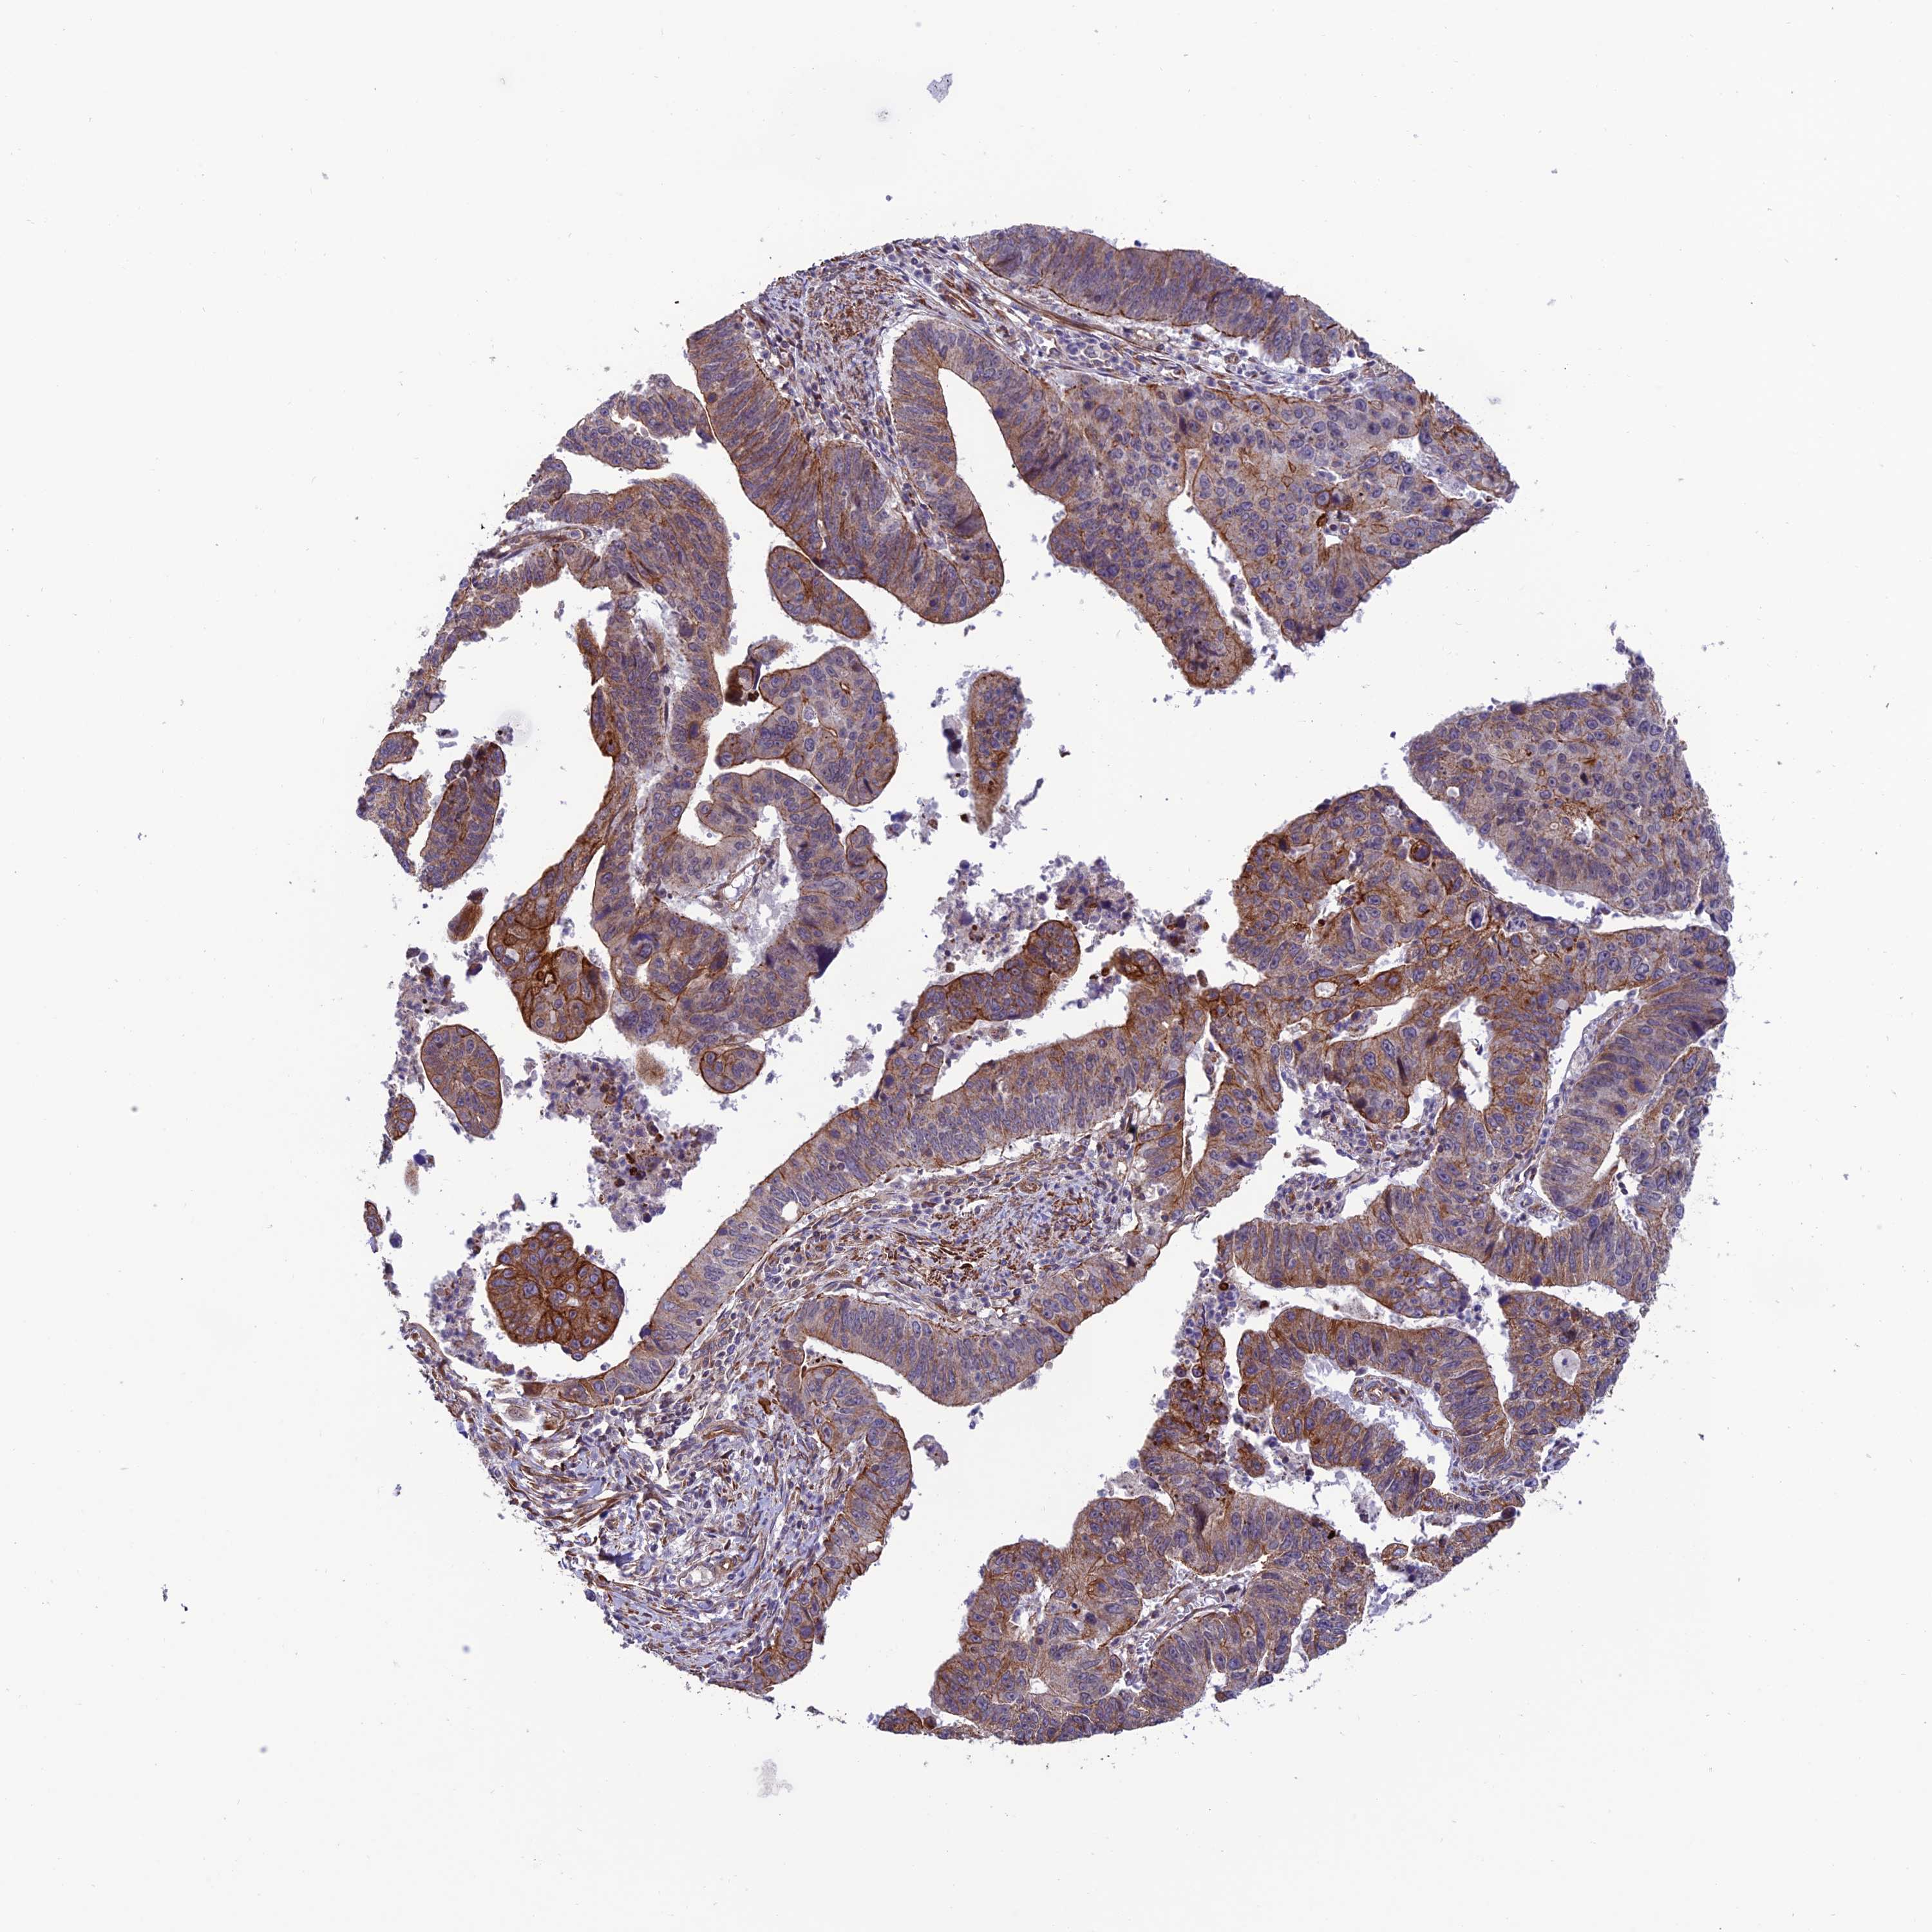

STOMACH CANCER - Protein expressioni

A mouse-over function shows sample information and annotation data. Click on an image to view it in a full screen mode. Samples can be filtered based on level of antibody staining by selecting one or several of the following categories: high, medium, low and not detected. The assay and annotation is described here.

Note that samples used for immunohistochemistry by the Human Protein Atlas do not correspond to samples in the TCGA dataset.

Antibody stainingi

Antibody staining in the annotated cell types in the current human tissue is reported as not detected, low, medium, or high, based on conventional immunohistochemistry profiling in selected tissues. This score is based on the combination of the staining intensity and fraction of stained cells.

Each image is clickable and will lead to virtual microscopy that enables deeper exploration of all samples and also displays staining intensity scores, fraction scores and subcellular localization as well as patient and tissue information for each sample.

Antibody HPA043063

Staining

High

Medium

Low

Not detected

Intensity

Strong

Moderate

Weak

Negative

Quantity

>75%

75%-25%

<25%

None

Location

Nuclear

Cytoplasmic/membranous

Cytoplasmic/membranous,nuclear

Adenocarcinoma, NOS